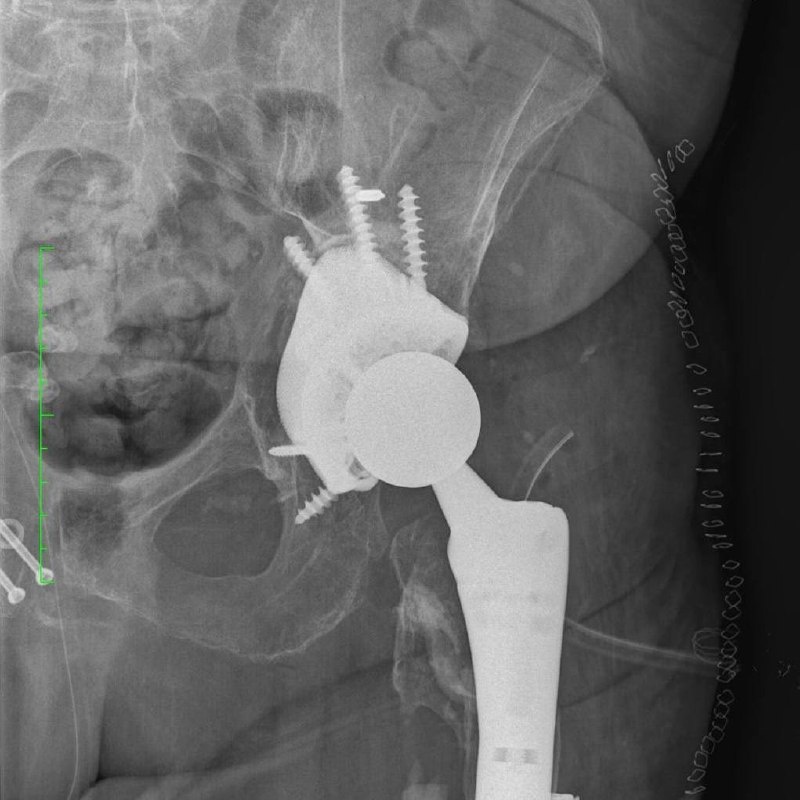

В НМИЦ фтизиопульмонологии и инфекционных заболеваний Минздрава России хирурги провели уникальную операцию пациентке, которая несколько лет страдала от тяжёлых последствий травмы таза и перипротезной инфекции.

После ДТП и нескольких операций у женщины сформировались обширные дефекты костей, из-за которых стандартные импланты уже не подходили. Риск повторной инфекции и потери функции сустава был крайне высок.

👨‍⚕️ Команда травматологов под руководством д.м.н. Ярослава Рукина приняла решение использовать индивидуальный титановый имплант, созданный на 3D-принтере по данным КТ. Конструкция идеально соответствовала анатомии пациентки, а заранее рассчитанные отверстия позволили точно установить фиксирующие винты, обеспечив стабильность.

👩‍⚕️ Операция прошла по заранее спроектированному плану. Уже на следующий день пациентка смогла встать и сделать первые шаги с ходунками. Через неделю её выписали домой в удовлетворительном состоянии.